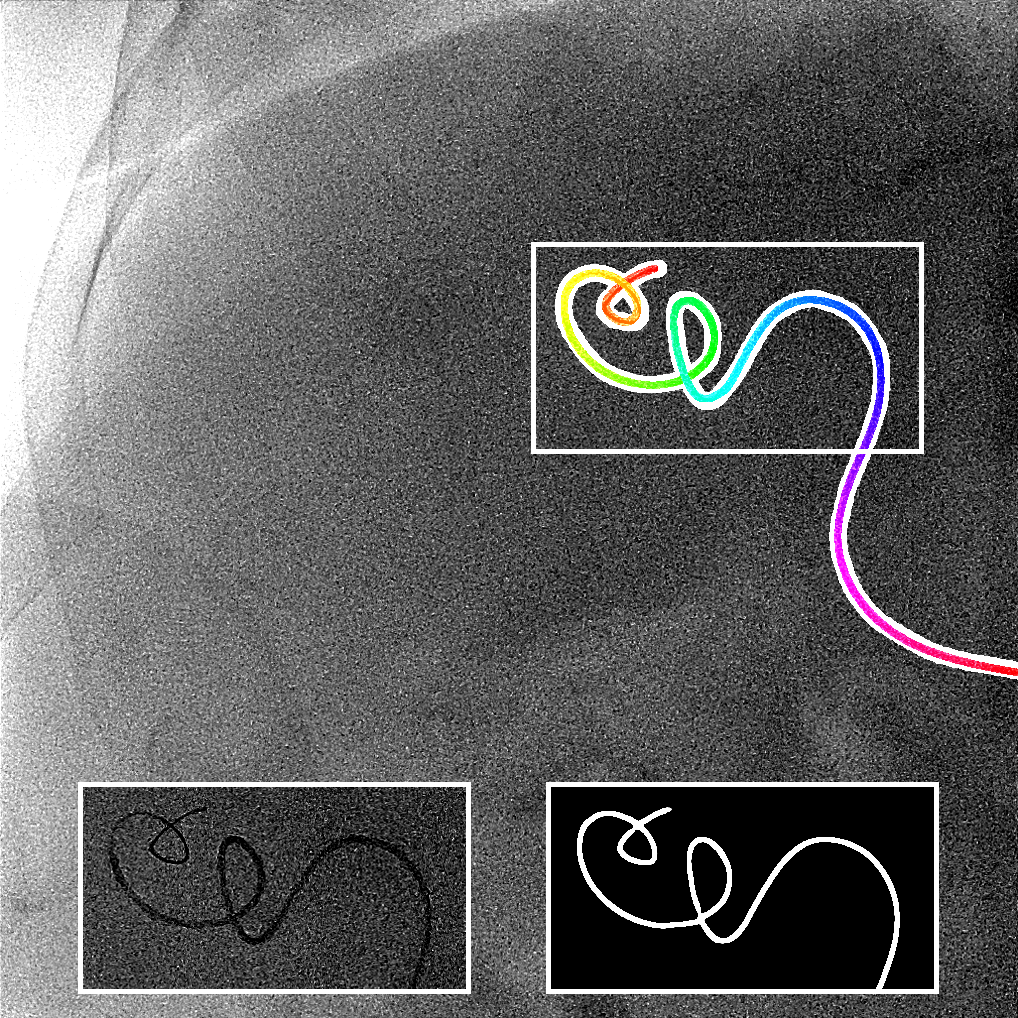

The output of the neural network is first thresholded with a threshold (between 0 and 1) and then skeletonized [19]. Next, the branches (ordered sets of pixels) are determined based on connectivity. Connection points are created between close branches. If the closest points between two branches are within a distance pixels, we consider this to be a possible connection, and there can be only one connection between two particular branches. Then, to link the branches, three steps are done (Fig. 2). First, for each connection, we divide and merge branches in order to have the longest branches. Second, loops are detected and merged following the direction at the crossing point. We have a loop in a branch when two points, within a distance pixels, have their distance along the branch of at least pixels. Before the third step, the first and second steps are repeated a second time with a distance superior to . Finally, in the last step, the remaining connected branches larger than pixels are considered as incomplete loops or straight loops due to foreshortening. We process them similarly as the second step by closing the two endpoints of their branch. When all the potential links have been processed, we keep the longest connected set of branches and choose amongst the two endpoints the farthest from the image border as the tip of the catheter centerline. Finally, the centerline is smoothed by fitting a spline.

We evaluate using the tip distance error (i.e. the distance between the annotated catheter tip and the tip of the segmented catheter), and the average distance between the manually segmented catheter and the automatically segmented catheter. Figure 3 shows the tip and catheter distances results. We compute the precision of the tip between consecutive frames. The median, average, minimum and maximum of the standard deviation per sequence of the tip distance error are respectively 0.7 mm, 4.9 mm, 0.1 mm and 55.7 mm. Five examples of segmentation are shown in Figure 4. In the third frame, the segmentation is going too far and follows part of the vertebrae. The fourth frame misses the proximal part of the catheter. The last frame is the only sequence with significant false positives. It is less noisy because it has been acquired with higher radiation dose. The neural network was not trained for such sequence.